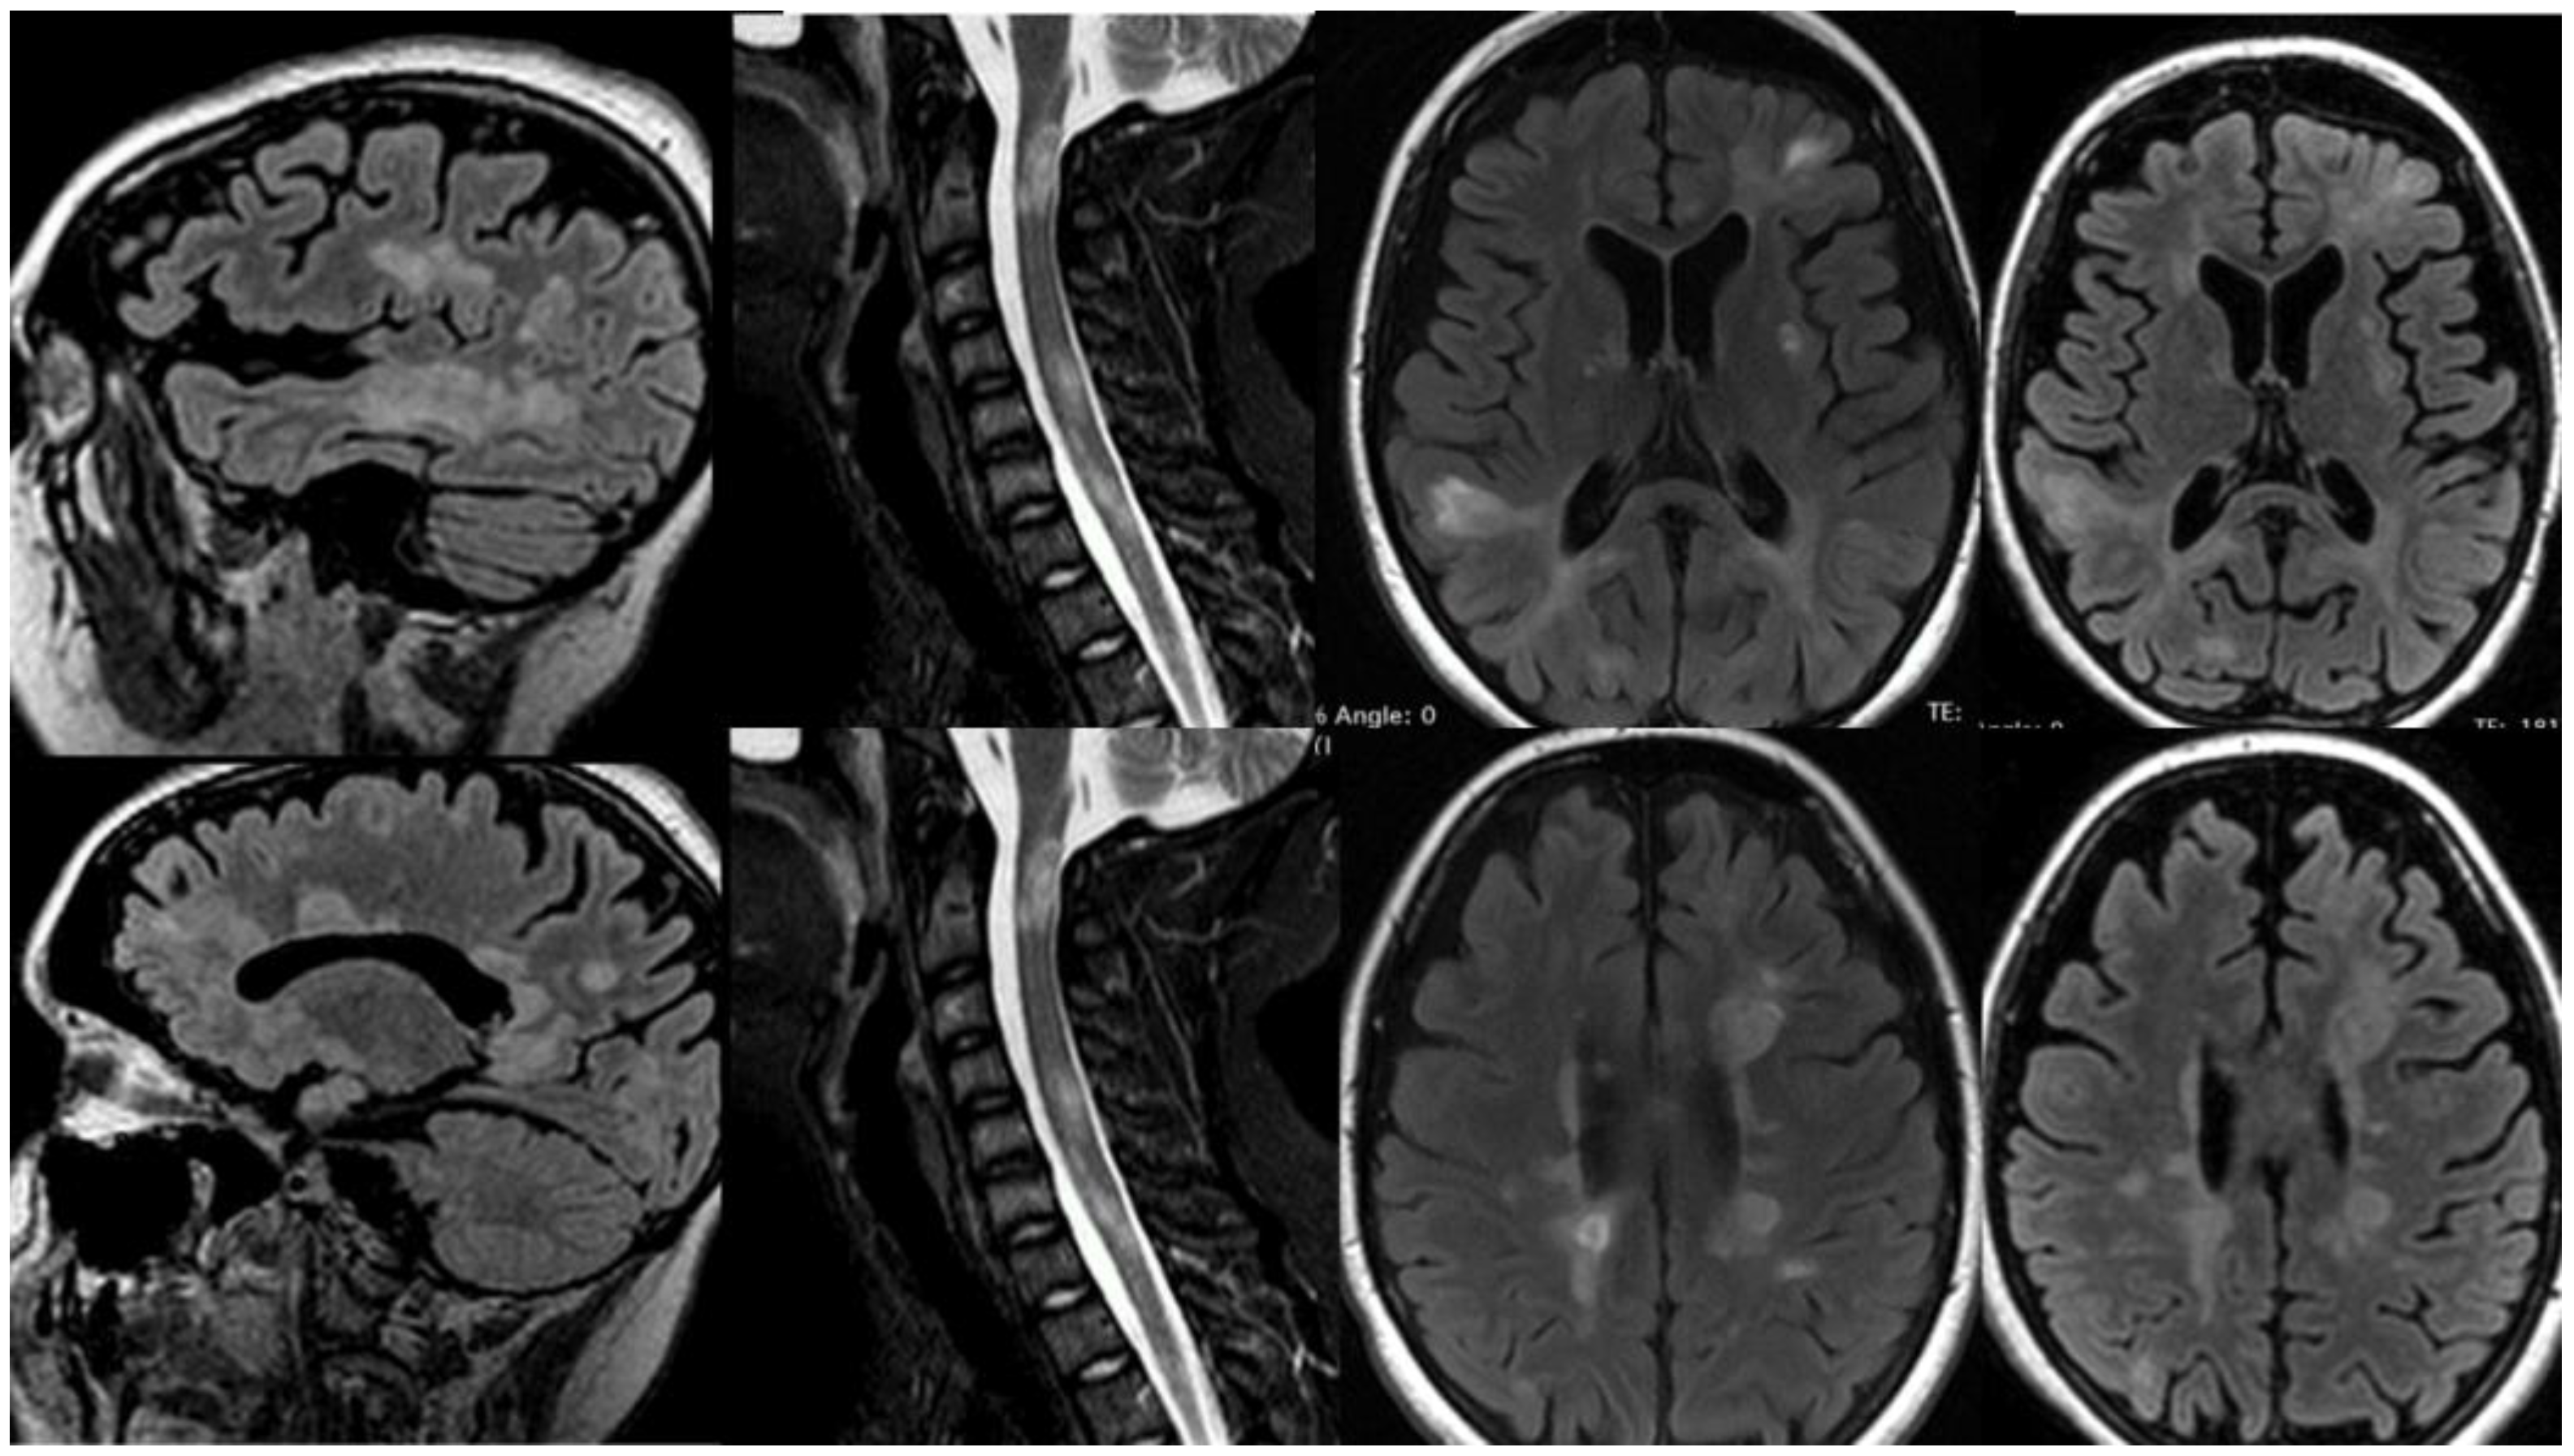

3.1.1. Patient 1

3.1.2. Patient 2

3.1.3. Patient 3